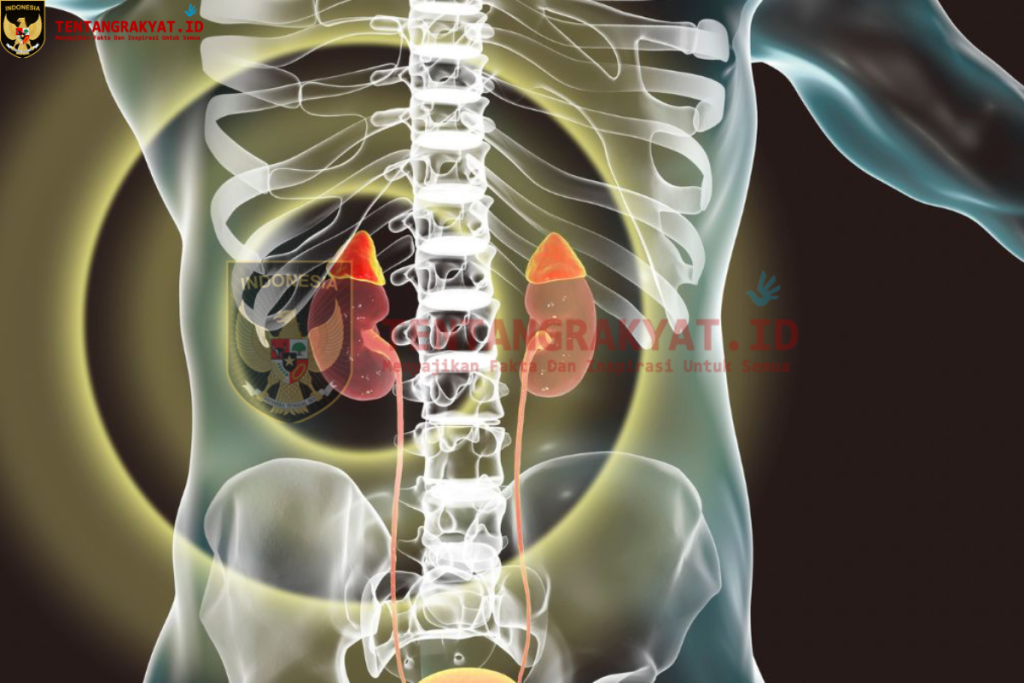

Awal Mula Kerusakan Ginjal

Hasil pemeriksaan lanjutan menunjukkan bahwa ginjal pasien tidak berfungsi dengan baik. Meski dokter memastikan bahwa tidak ditemukan indikasi kanker, gangguan pada ginjal menjadi salah satu dampak paling serius dari kondisi tersebut.

Ginjal yang bekerja menyaring limbah dalam darah harus bekerja lebih keras untuk mengatasi kadar kalsium yang terlalu tinggi. Dalam jangka waktu tertentu, kondisi ini dapat menyebabkan kerusakan fungsi ginjal.

Dampak Kelebihan Vitamin D terhadap Ginjal

Ginjal merupakan salah satu organ yang paling rentan terdampak oleh keracunan vitamin D.

Ketika kadar kalsium dalam darah meningkat, ginjal harus bekerja lebih keras untuk menyaring kelebihan mineral tersebut.

Seiring waktu, penumpukan kalsium dapat menyebabkan pembentukan batu ginjal serta kerusakan jaringan ginjal.

Dalam beberapa kasus, kondisi ini dapat berkembang menjadi cedera ginjal akut atau bahkan gagal ginjal jika tidak segera ditangani.